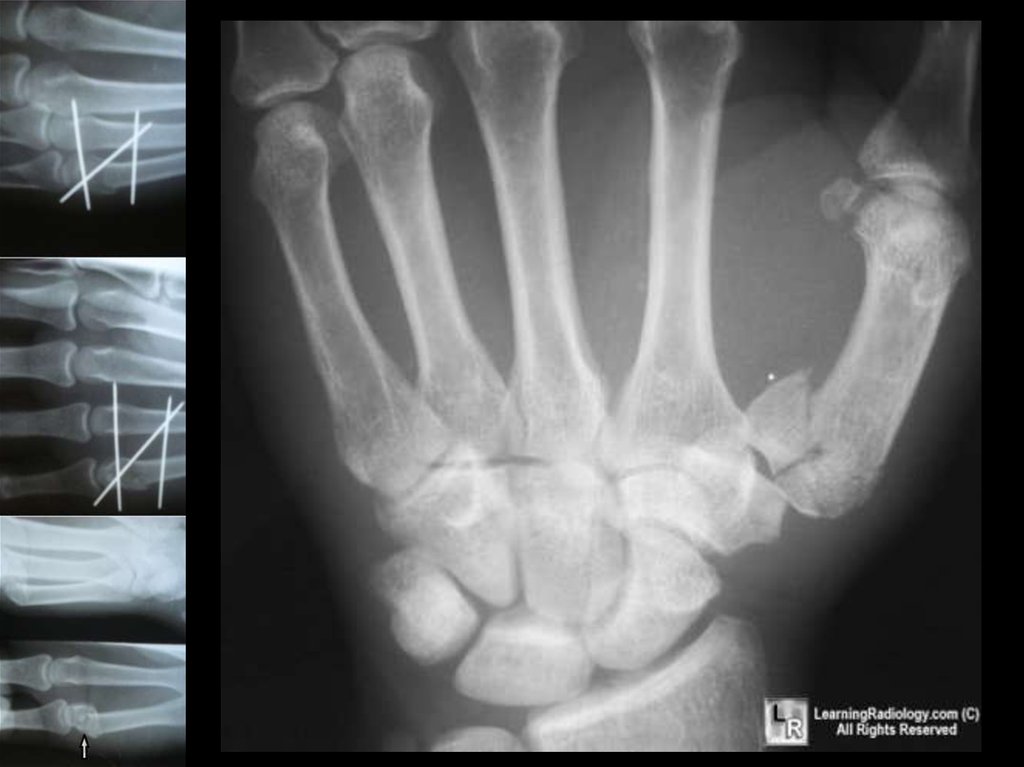

7. Перелом первой пястной кости

Перелом Беннета

Возникает в результате удара,

направленного по оси I пальца.

При этом происходит вывих в запястнопястном сочленении с одновременным

переломом основания I пястной кости,

которая, смещаясь кверху, отламывает

треугольный фрагмент ульнарного края

собственного основания.

Таким образом, перелом Беннета

правильнее называть переломовывихом I

пястной кости.

10. Лечение (Хирургическое)

Если вправления не получилось,

следует повторить попытку или

направить больного в стационар, где

возможно применение скелетного

вытяжения или хирургических методов

лечения.

При неудачных попытках вправления

применяют скелетное вытяжение или

фиксацию спицей Киршнера костным

аутошипом.